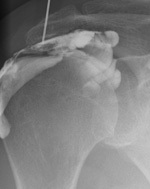

- La capsulite rétractile, à condition que l’injection soit vraiment faite dans l’articulation. Au besoin cette injection sera faite sous contrôle radiologique pour être sûr que l’aiguille se situe bien dans l’articulation.